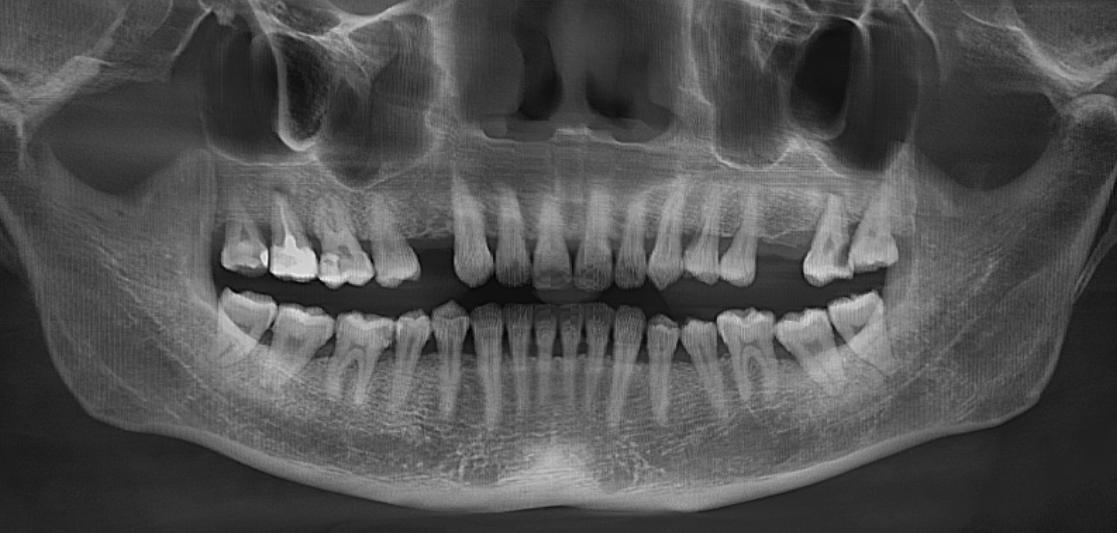

(种植术前全景片)